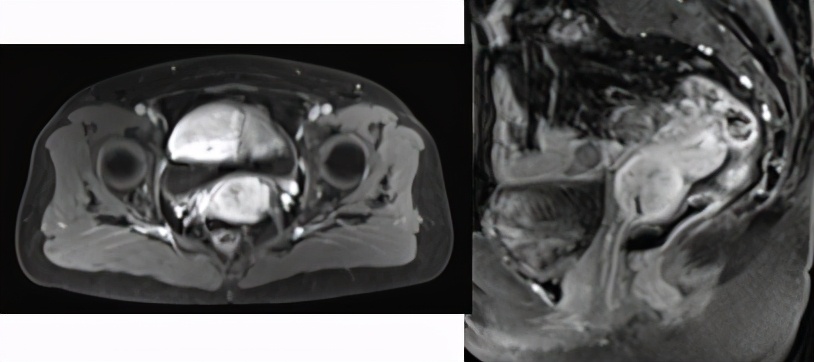

2013-02-18盆腔MRI示:宫颈占位,侵犯阴道后穹窿,盆腔淋巴结未见明显肿大。

治疗前MRI(2013.2)

放疗后MRI(2013.6)